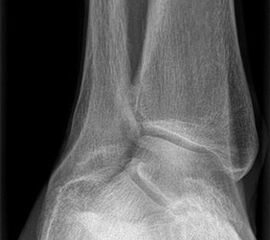

Auf dem linken Bild (a) Varusarthrose des oberen Sprunggelenks mit deutlicher Mehrbelastung der medialen Gelenkanteile. Dort bereits deutlich sichtbarer Knorpelverlust. Rechtes Bild (b) Valgusarthrose des oberen Sprunggelenks. Erhöhte Druckbelastung in de

Abbildung 1

Es wurde in der gleichen Arbeit auch das Alignement der arthrotischen Sprunggelenke untersucht. Insgesamt lag nur in 37% der Fälle ein physiologisches Alignement vor, 55% der Gelenke waren varisch eingestellt, 8% valgisch.